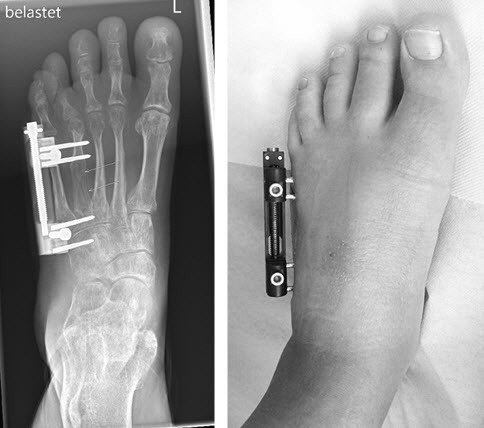

Therapie

Es erfolgt eine schrittweise Verlängerung des 4. Mittelfussknochens mit einem kleinen Fixateur.

Nach der Operation

Nach 4 Monaten wird der Fixateur entfernt. Es besteht ein sehr ansprechendes funktionelles und kosmetisches Resultat.